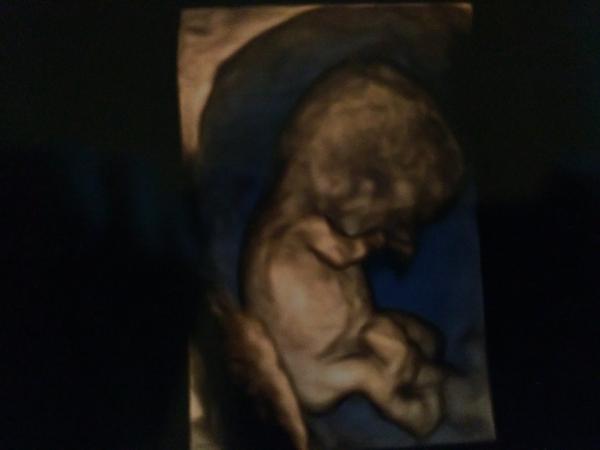

@babydesire jehooo to je krásna fotka tiež by som takú chcela 🙂 ako pekne spinká 🙂

@gabuchah no,krasna ja viem,,keby to boli zadara vypytam si taku vzdy ked mi robil sono..idem buduci stvrtok do poradne,tak snad ho kukne a vypytam si novu fotku,,predsa uz budem skoro v polovicke tehu 🙂

@babydesire teda za takúto by som 5e kľudne dala vždy, naozaj pekná... Veď obyčajná stojí euro a ľubka dokonca platila 7 🙂 normálne som.Sa namotala na toto 3d sono 🙂

@babydesire tak si predstavujem 3d foto 🙂:krasne

Ano,spravil nam krasny obrazok vtedy,tiez ma to prekvapilo ze 3D foto,,xixi,ja som dovtedy videla len tie klasicke ciernobiele 🙂) celu cestu domov som sa nan divala 🙂)) a potom aj doma..aa moj otec povedal,ze jeee cely dedo 😀 je takisto holohlavy ,, a priatelova maminka si tu fotecku prilozila k licu a tak sa snou pohladila,taky trosku nepriamy ale mily prvy kontakt s vnucatom 🙂

@babydesire to aom netušila že aj takto sa fotky dajú urobiť :#) Juuj,aj ja scem teraz takú 🙂

@gabuchah Hmm,ja som si myslela,ze je to dnes uz bezne,,az potom tu kukam a kazda fotka co som tu videla len take klasicke...skus sa spytat gynekologa ci ti vie spravit aj taku